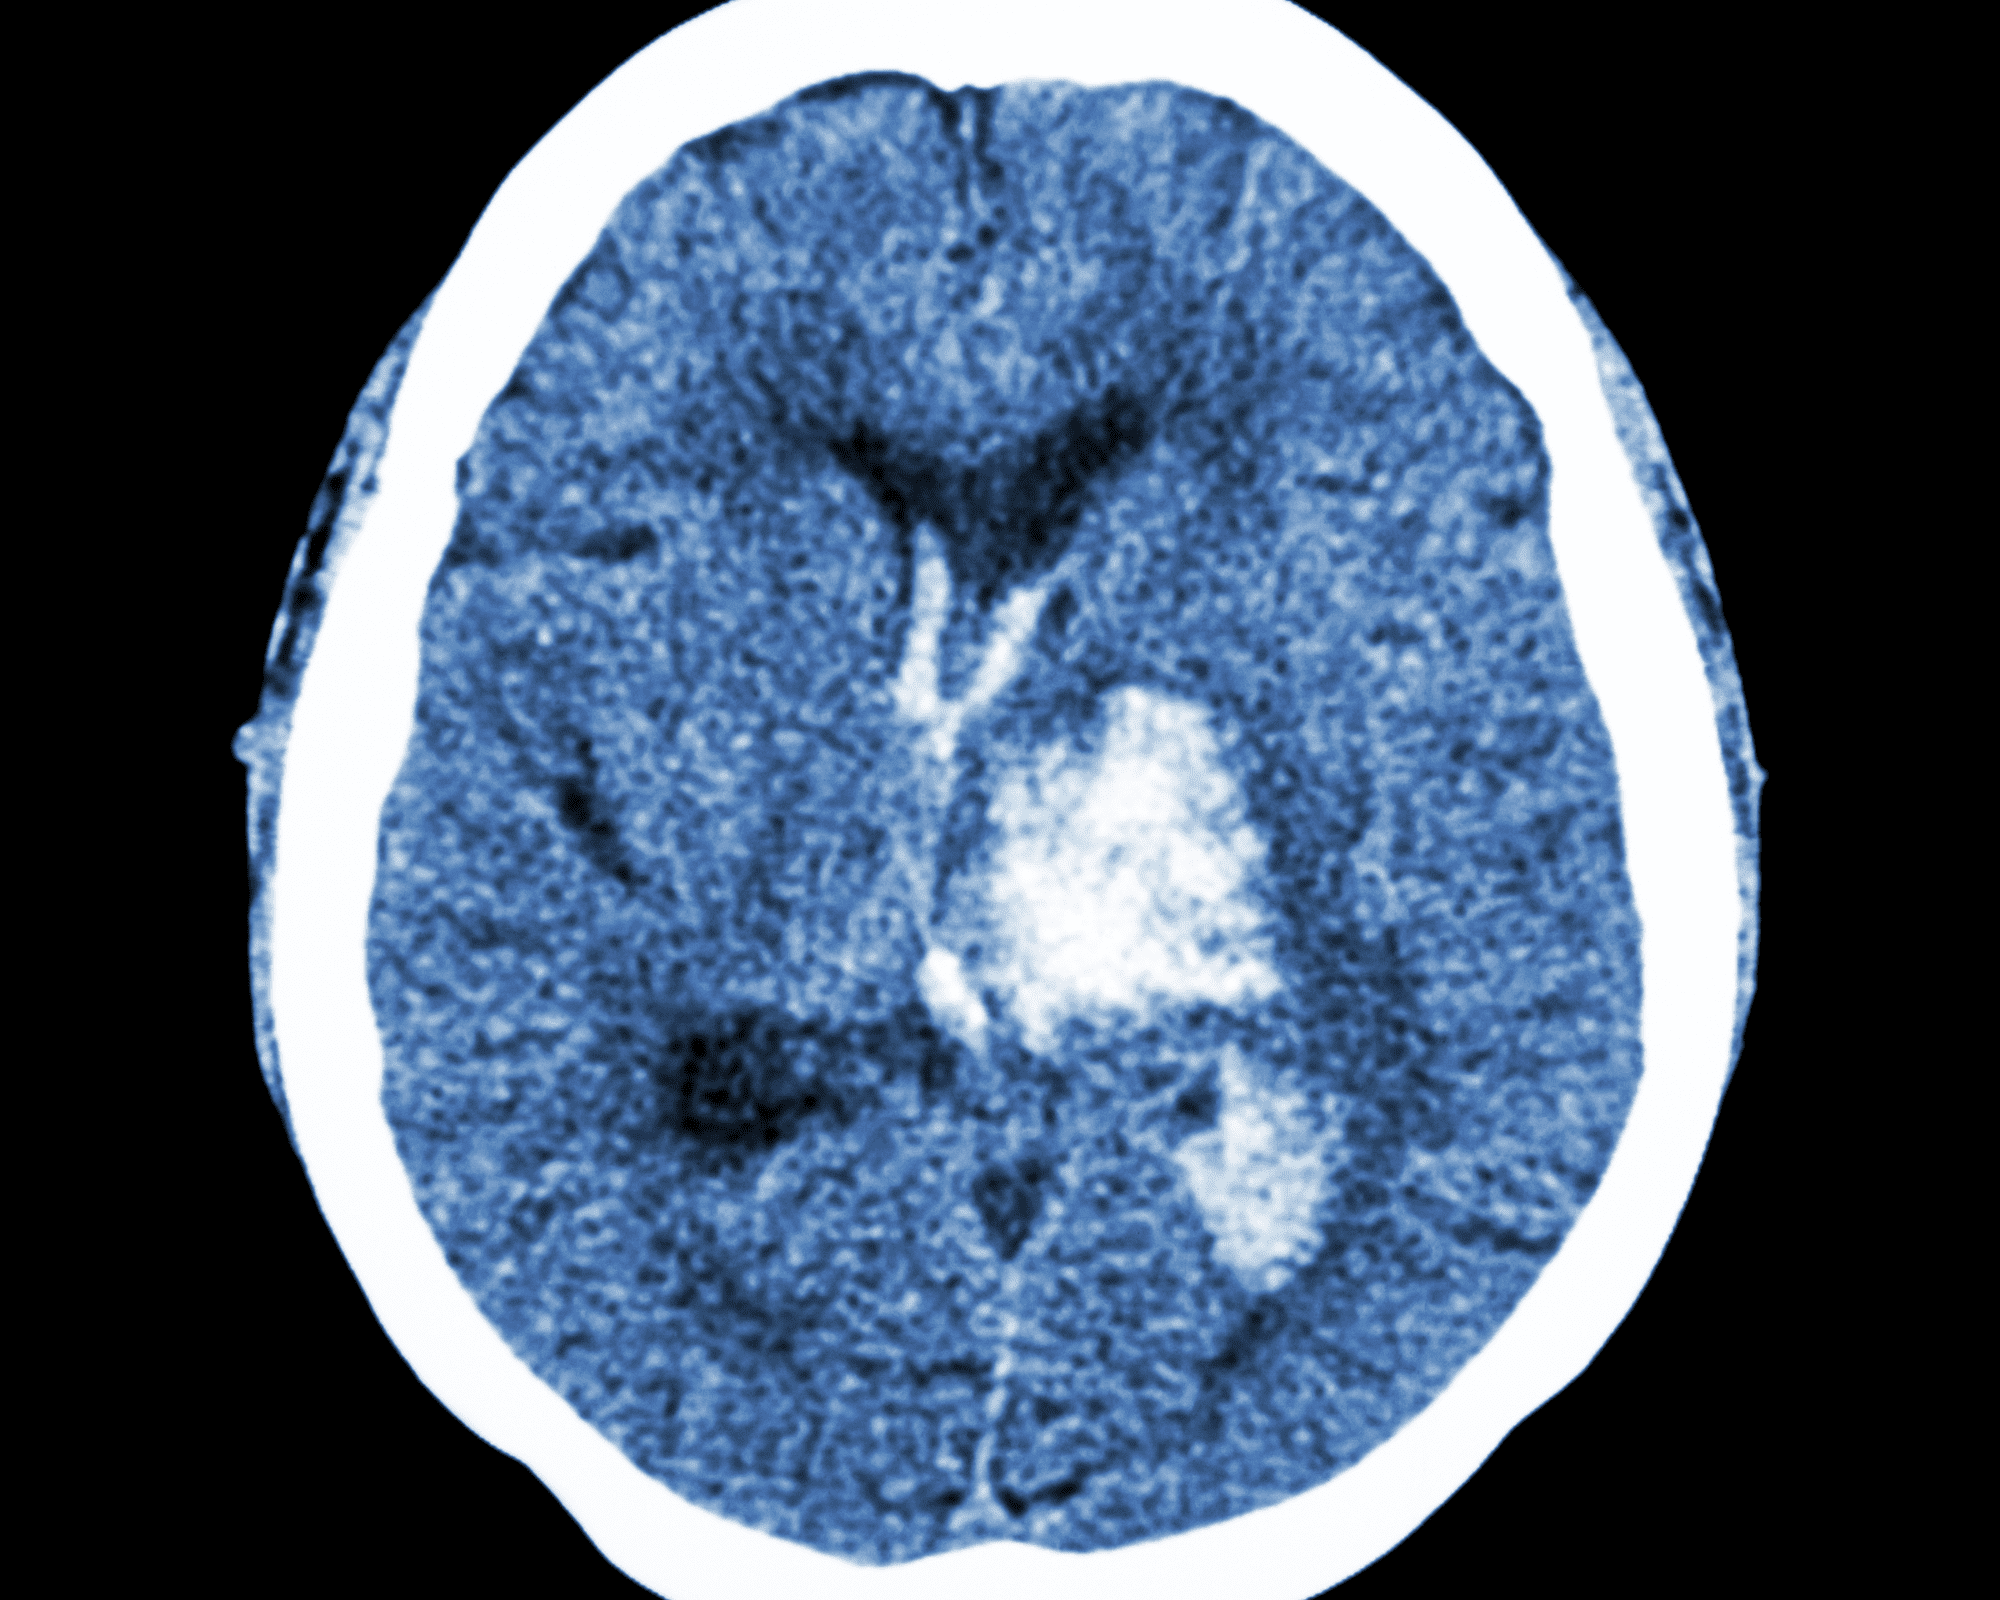

To reduce the lasting effects of ischaemic stroke caused by a blood clot, medication to dissolve the clot (intravenous thrombolysis [IVT]) should be administered within three hours, or up to four-and-a-half hours in some people, after symptoms begin. Mechanical removal of the clot (endovascular therapy [EVT]) may be safe for some people up to 24 hours after stroke symptoms start as well. However, not all people experiencing a stroke have rapid access to these treatments, the statement adds.